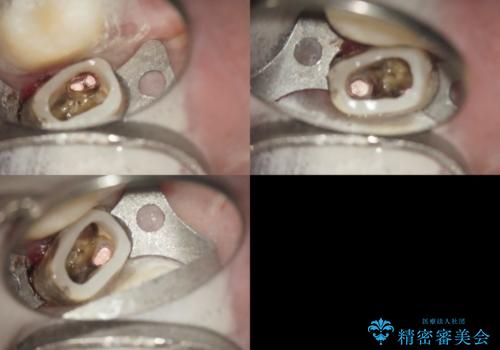

- 歯周外科による歯肉・歯の相対的な位置関係の改善

→治癒待ちの間に再根管治療、ファイバーコアの築造

根管治療や歯周外科などは、患者さんのモチベーションにあまり寄与しない反面非常に重要度が高い。これをいかに理解していただいて、労力を割くかどうかで、今後の歯のもちに大きな違いがあるといえる。